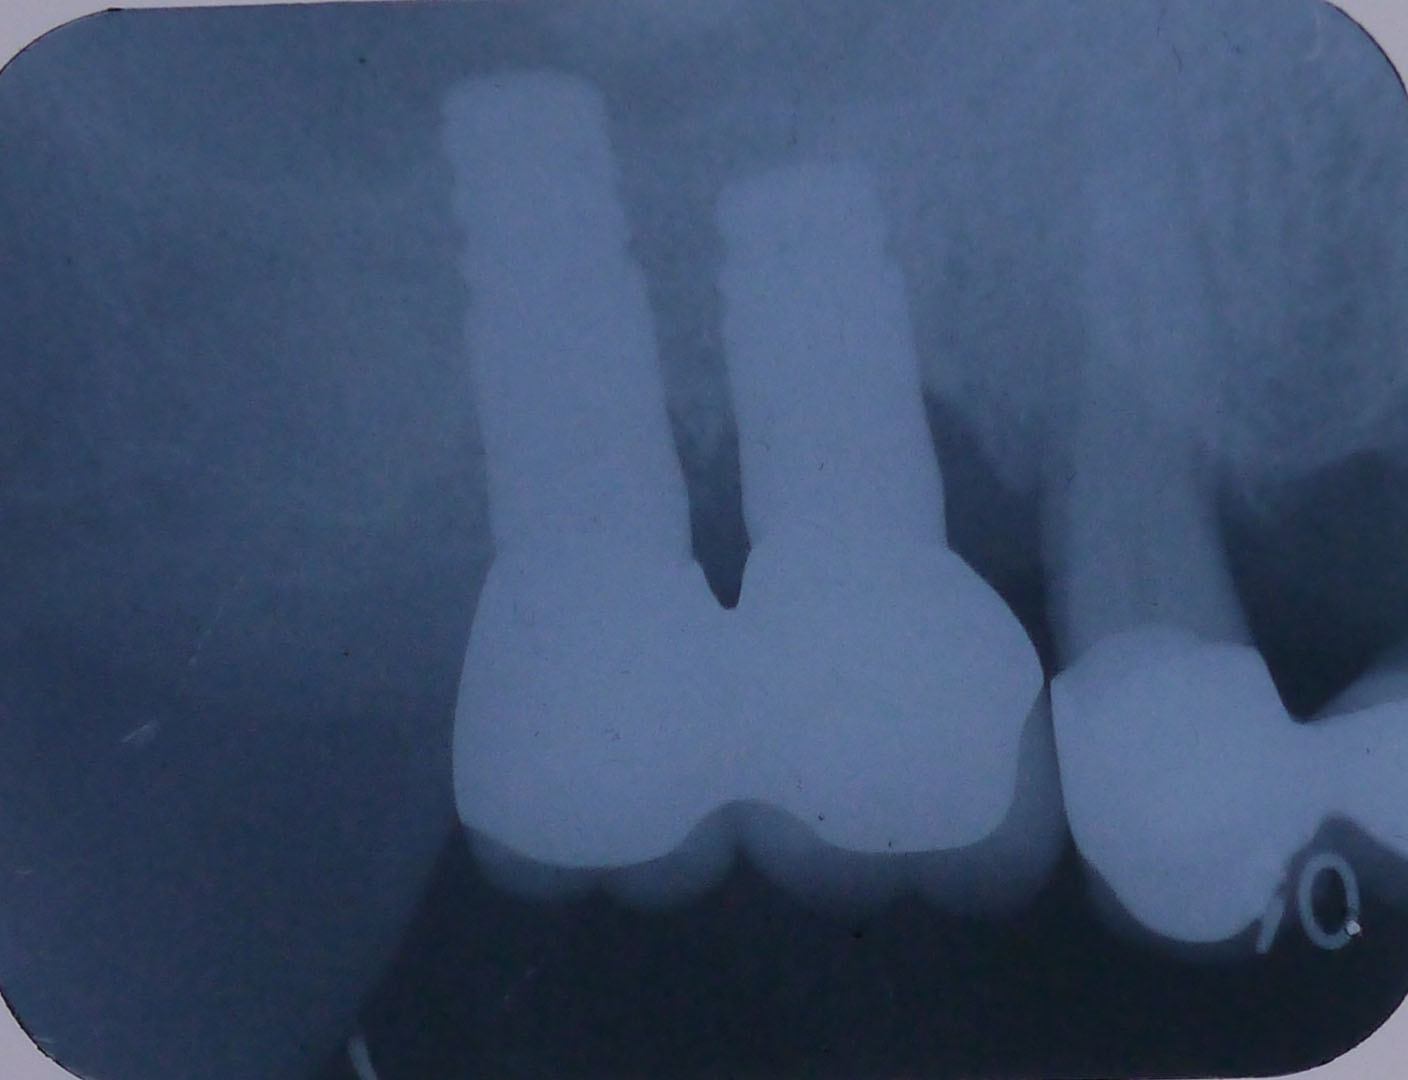

レントゲン画像1

平成24年9月11日の手術後のレントゲン画像

レントゲン画像2

平成25年1月16日、4ヶ月後のレントゲン画像